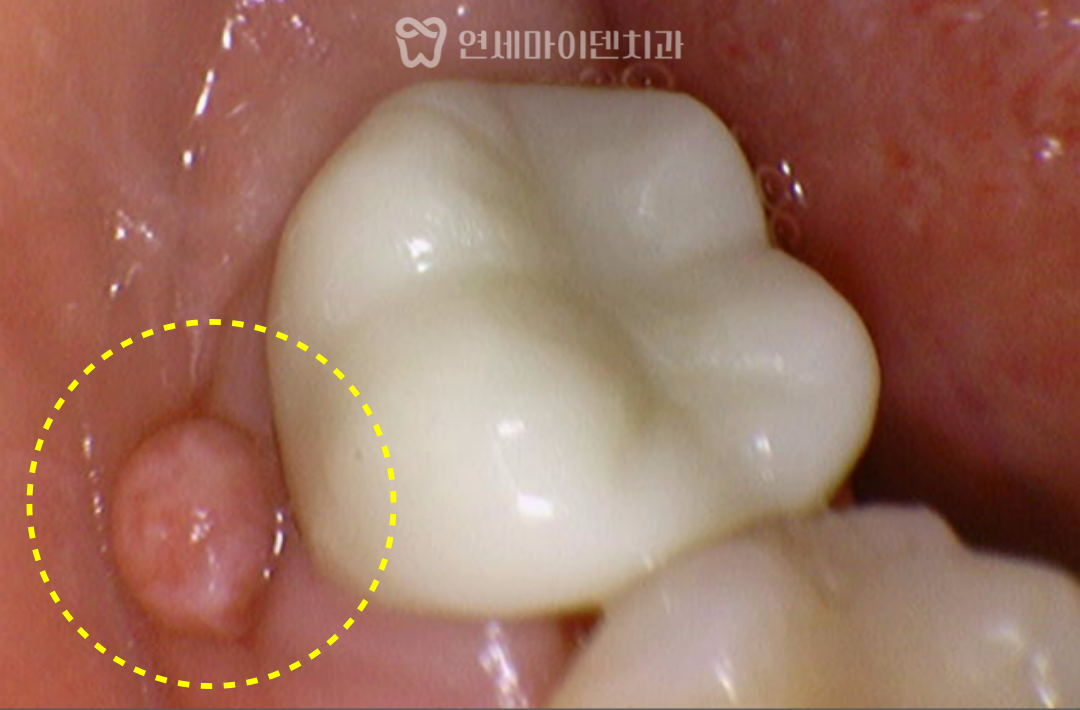

내원 당시 잇몸에는

여드름처럼 보이는 고름 주머니가 있었고,

비슷한 시기에 잇몸에 염증성 여드름이 나타났습니다.

초기 영상에서는 염증 범위가 다소 넓게 나타났으며,

크랙은 확인되지 않았습니다.